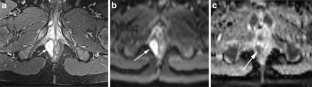

Perianal complications of Crohn disease are a common occurrence in children and can result in significant morbidity when not accurately characterized prior to surgical intervention. MRI is an excellent imaging modality for the evaluation of perianal inflammatory bowel disease – allowing characterization and detailed description of perianal fistulas. MRI has many advantages over other imaging modalities for the pediatric patient. Radiologists will benefit from a sophisticated understanding of perianal anatomy, the classification of perianal fistulas, the advantages MRI offers in characterization of perianal fistulas as well as the common and incidental findings that are important in the MRI evaluation of perianal inflammatory bowel disease in children. Perianal fistulas are found at a high rate in pediatric referrals and are more commonly found in male patients.

Fig. 4